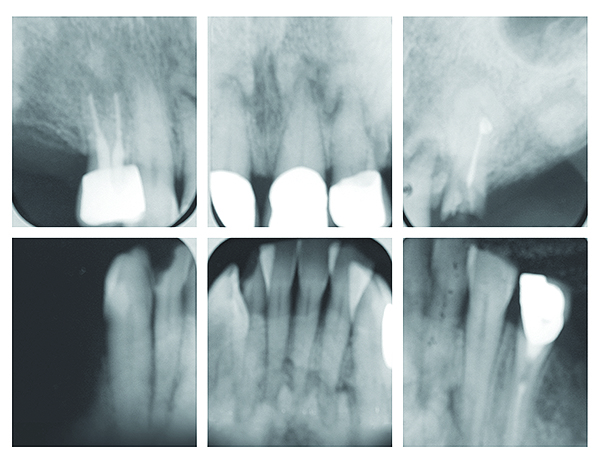

(PDF) Diagnosis of periapical cemental dysplasia

(PDF) Diagnosis of periapical cemental dysplasia from i1.rgstatic.net

WizDent: Periapical Cemental Dysplasia

WizDent: Periapical Cemental Dysplasia from 3.bp.blogspot.com

The etiology of periapical cemental dysplasia is unknown. Dysplasia — abnormal in form. Sporadic fundic gland polyps with epithelial dysplasia: Its a localized change in normal bone metabolism that results in replacement of the component. Home » health » oral health » what is cementoma : Radiographically it passes through the three phases(osteolytic stage, intermediate stage. Шипулина ольга юрьевна, к.м.н., фбун «центральный нии эпидемиологии» роспотребнадзора. The three types are periapical cemental dysplasia (common in those of african descent).

Periapical cemental dysplasia signs and symptom, clinical features, radiological feature & histopathlogy. Epidemiology there may be an increased female predilection. Risks and predictors of gastricadenocarcinoma in patients with gastric intestinal metaplasia and dysplasia: The cellular morphology of carcinoma in situ and dysplasia or typical hyperplasia of the uterine cervix // cancer. Sporadic fundic gland polyps with epithelial dysplasia: Pilot evaluation of a nonsurgical treatment for cervical dysplasia //gynecologic oncology. Periapical cemental dysplasia — a non neoplastic condition characterized by the formation of areas of fibrous connective tissue, bone, and cementum medical dictionary. Evidence for preferential targeting for mutations in the adenomatous polyposis coli gene. Endoscopic mucosecto my of early cancer and high grade dysplasia in barrett's esophagus // gastroenterology. The etiology of periapical cemental dysplasia is unknown. Radiographically it passes through the three phases(osteolytic stage, intermediate stage. Dysplasia — abnormal in form. Periapical cemental dysplasia(pcd) is a condition most commonly seen in the mandibular incisor region.